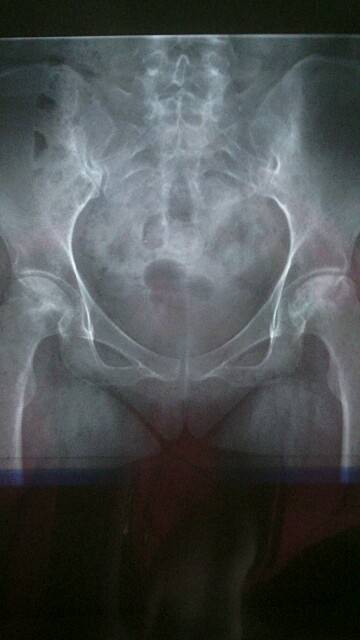

我拍的X光,可以做个对比

从片子看还没有塌陷,

我现在左腿属于三期,右腿属于二期。希望以后不要发展,我便知足。供大家参考,辨认骨坏患者自己属于几期。